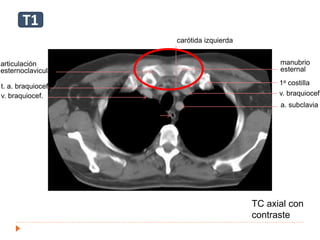

 Unión esternoclavicular: t1

v. braquiocef.

T

E

a. subclavia

carótida izquierda

t. a. braquiocef.

manubrio

esternal

1a costilla

articulación

esternoclavicular

TC axial con

contraste

T1